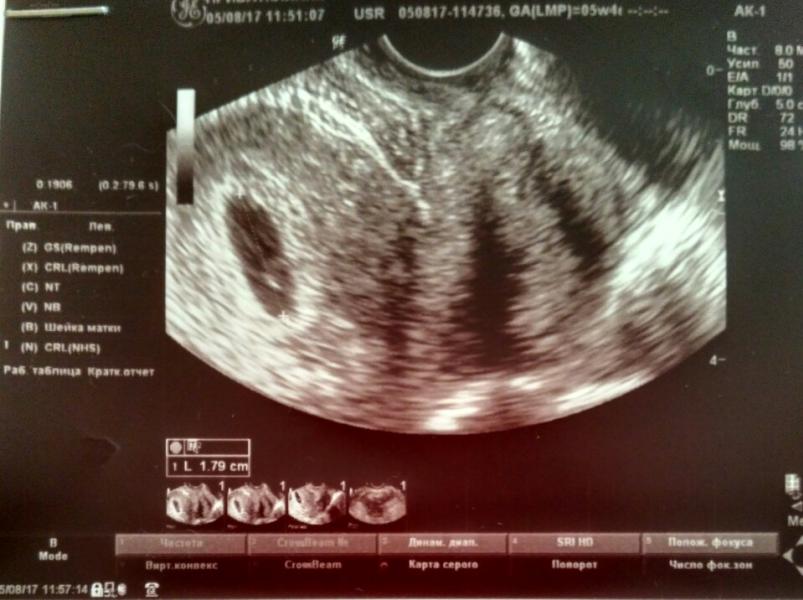

Первое УЗИ, на сроке 5 недель и 4 дня. Сердцебиение прослеживается, плод в матке, так что пью витамины и жду постановки на учёт. УЗИ проводилось в Приватклиник Лобня, узист Баранов С.В. (на вид недавно работает, на заключении сверялся с записной книжкой😁).